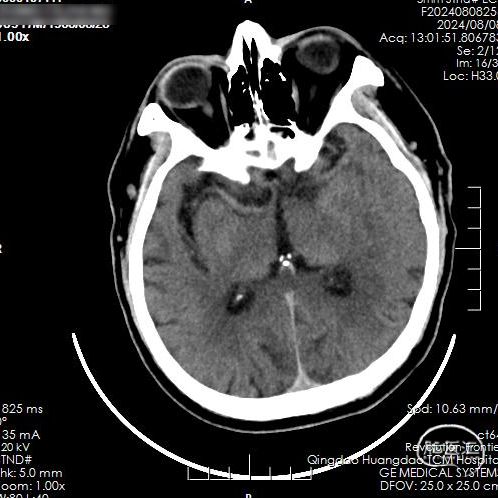

CT平扫:未见急性脑梗死早期病灶显影,未见大脑中动脉高密度征。

术后即刻复查脑CT,未见出血及梗死病灶。